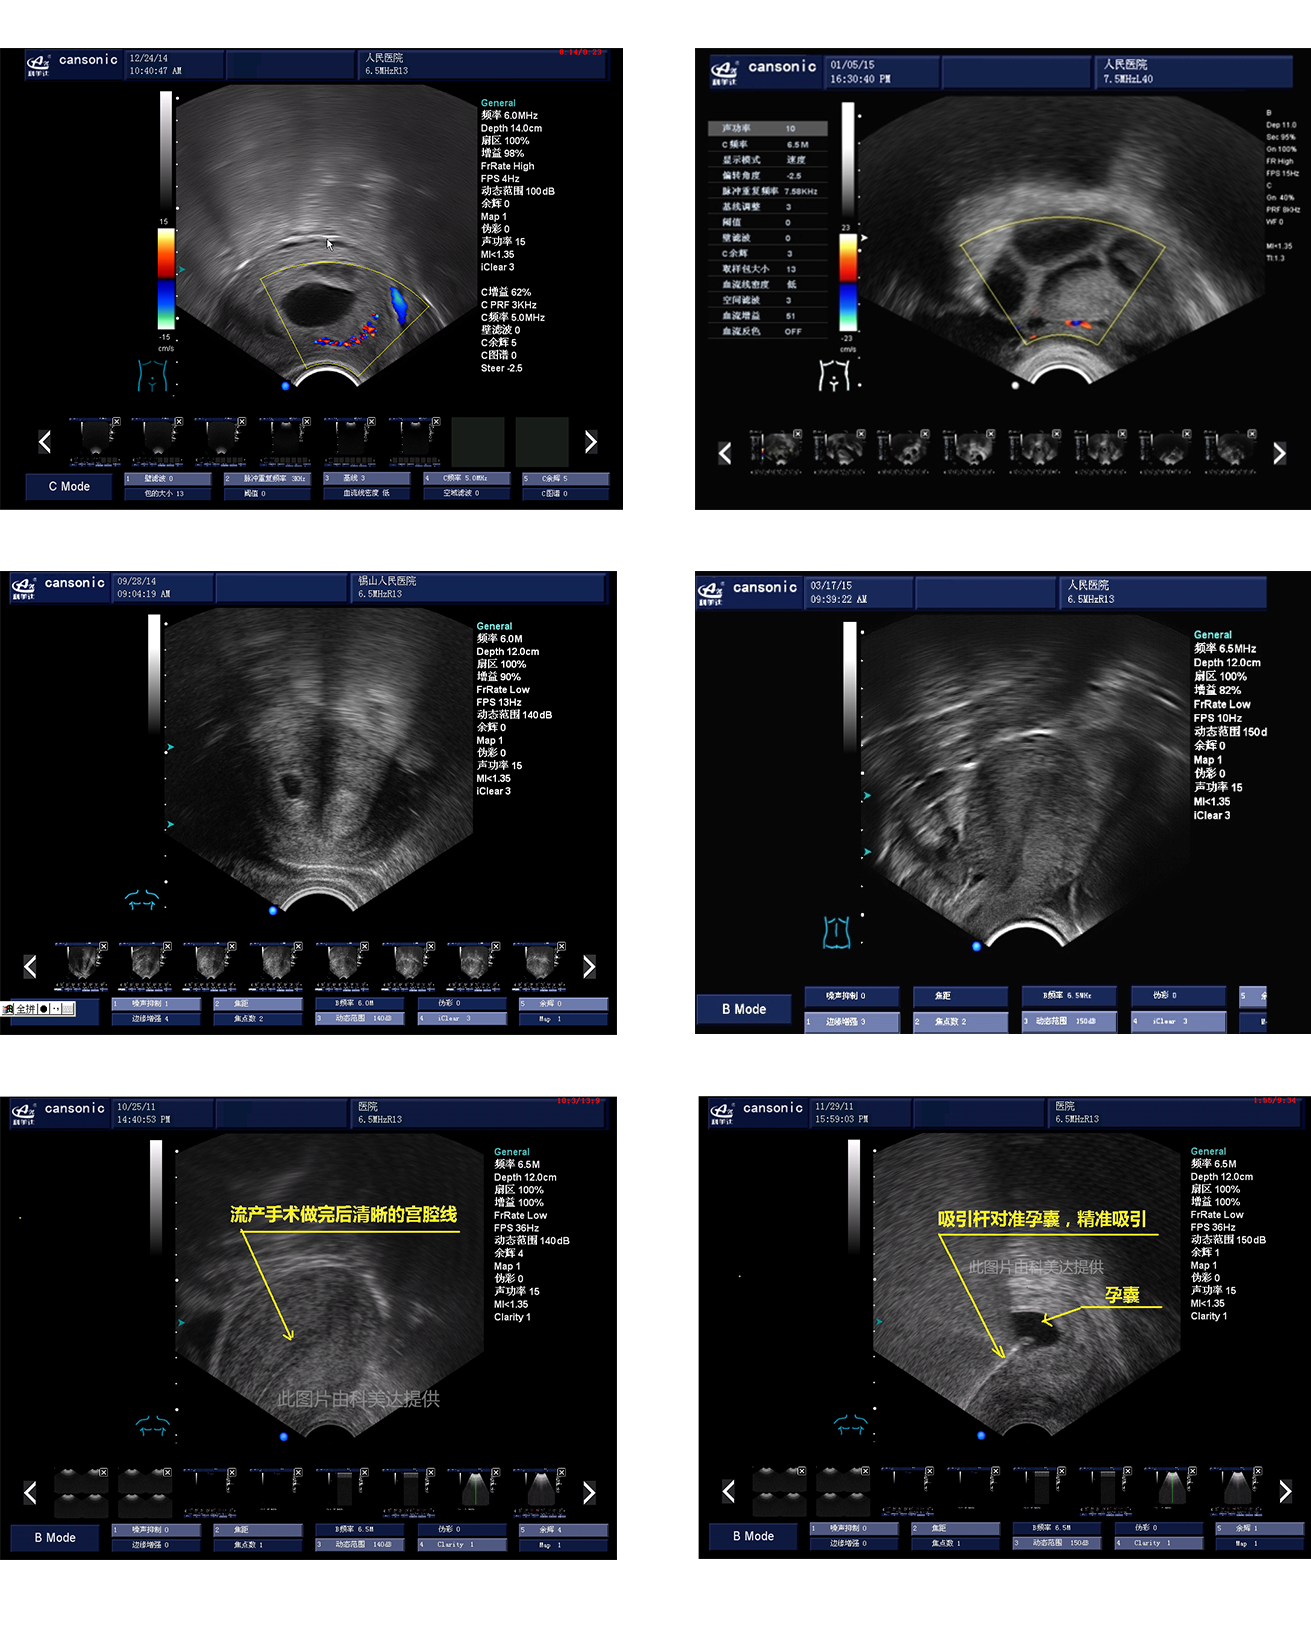

臨床圖示